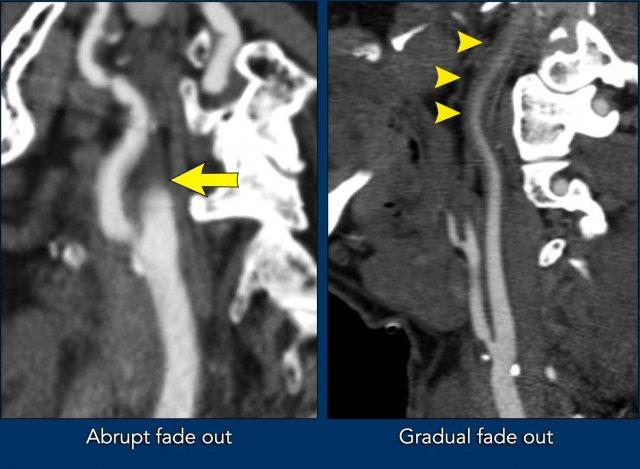

Hai trường hợp tắc nghẽn giả động mạch cảnh.

Trong trường hợp đầu tiên (bên trái), thuốc cản quang dừng khá đột ngột, mặc dù có thể thấy một vùng nhỏ với tỷ trọng thuốc giảm dần.

Trong trường hợp này, việc phân biệt giữa tắc nghẽn giả với lóc tách thành mạch hoặc tắc nghẽn do xơ vữa có thể khó khăn.

Tuy nhiên, chúng ta không thấy hình dạng ngọn lửa điển hình của xoang cảnh như trong lóc tách thành mạch, và không có dấu hiệu xơ vữa động mạch (không có mảng xơ vữa hay vôi hóa).

Trong trường hợp thứ hai, tỷ trọng thuốc cản quang giảm dần rõ ràng trên một đoạn dài hơn (đầu mũi tên).

Đây rõ ràng là tắc nghẽn giả động mạch cảnh.